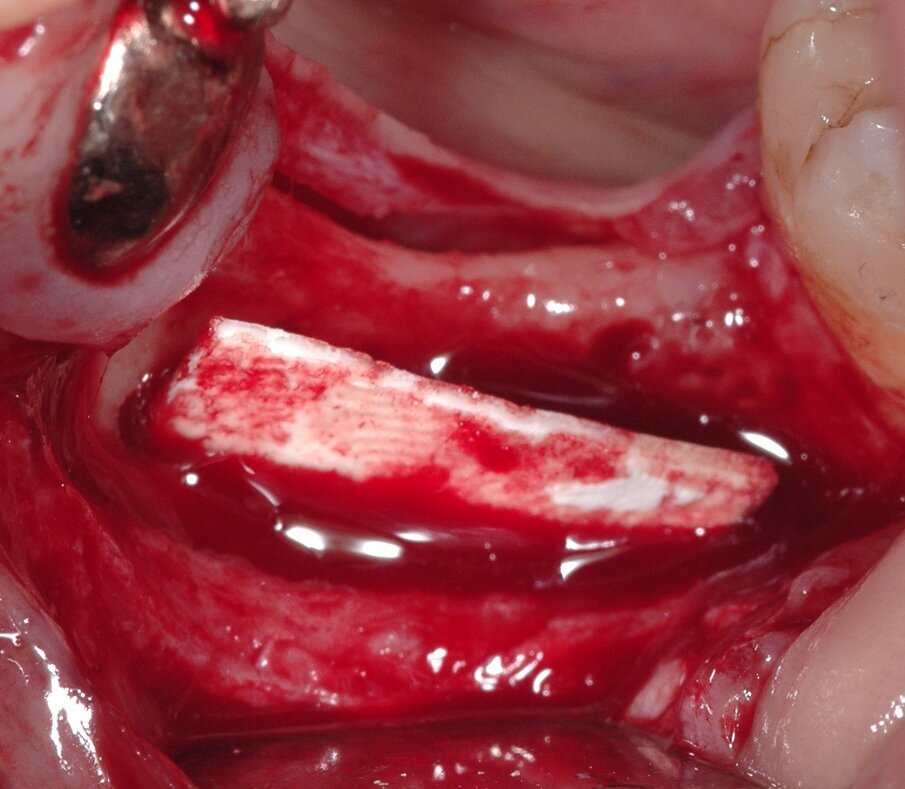

Questa particolare tecnica si basa sull’applicazione di una lamina corticale inserita in una fessura chirurgica sul margine declive del difetto senza l’utilizzo di viti, pin o adesivi. Con un follow-up di 8 mesi, gli Autori hanno eseguito le analisi istologiche e istomorfometriche e una valutazione radiografica della dimensione della cresta. 20 pazienti (9 uomini e 11 donne, di età compresa tra 52 e 76 anni) sono stati arruolati nello studio e trattati per riabilitazione implantare abbinata alla tecnica “Bone into Bone”. Una lamina dura (OsteoBiol Lamina, Tecnoss) viene modellata ed inserita nella fessura chirurgica, in modo da creare un spazio riempito con una miscela 1:1 di eterologo collagenato suino osso e particelle ossee autologhe. L’area innestata viene quindi coperta con membrana in collagene riassorbibile prima di suturare il lembo (Figg. 1, 2).